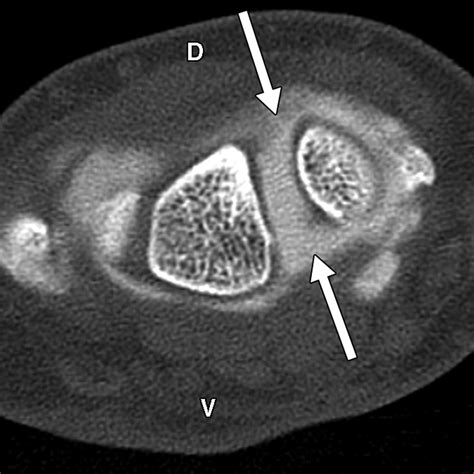

Diagnosing this condition requires a comprehensive physical examination combined with advanced imaging. Physicians typically rely on standard X-rays, which often reveal the characteristic gap in the scaphoid and the narrowing of the joint space. In more complex cases, a CT scan or MRI may be ordered to assess the exact degree of cartilage degradation and to plan potential surgical interventions.

• scaphoid nonunion advanced collapse radiology